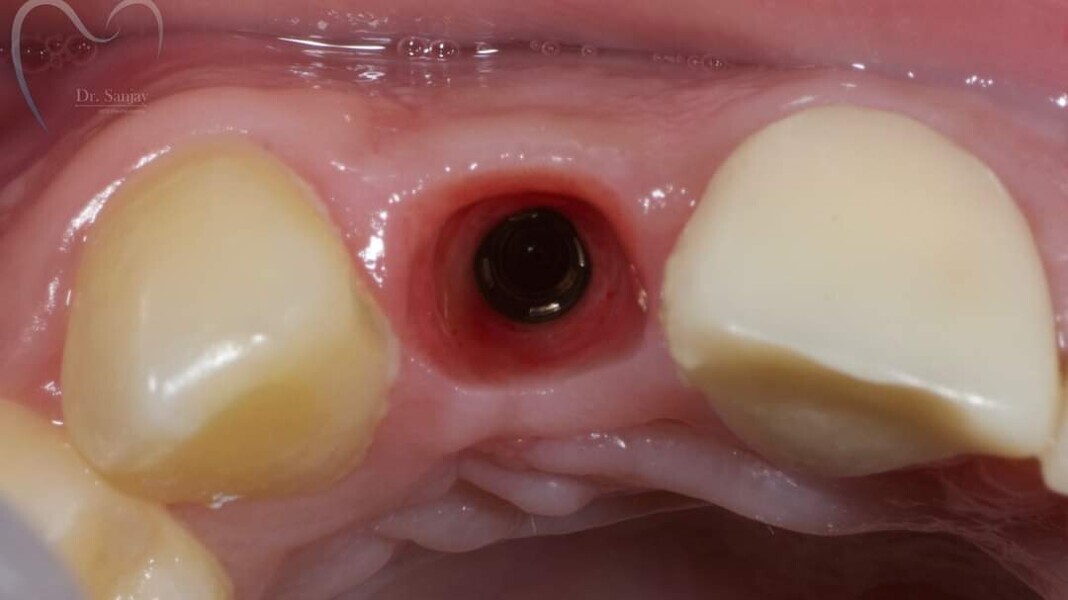

Esthetic Rehabilitation of Maxillary Anterior Teeth: Dr Sanjay Sah